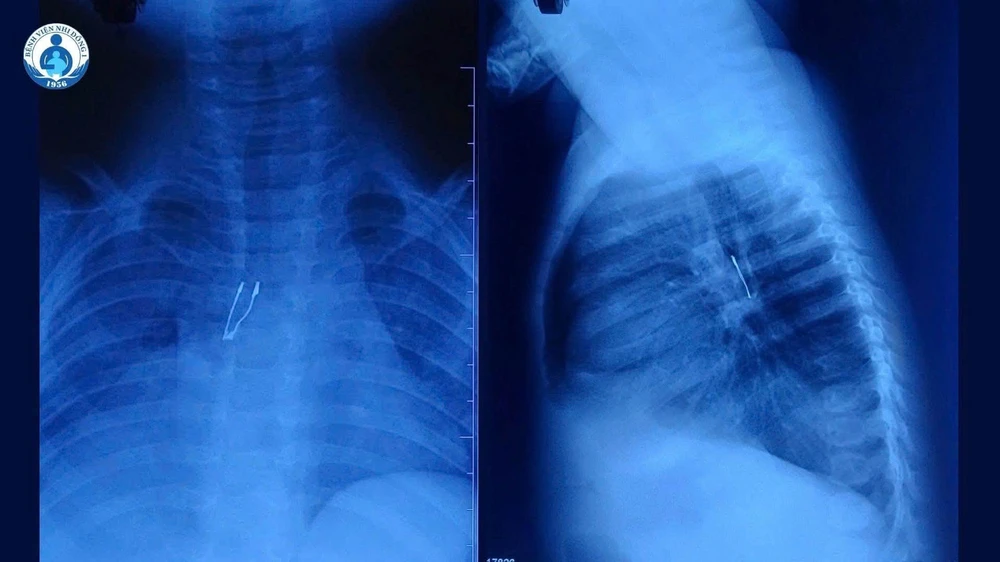

Dị vật nghi ngờ là một bóng đèn LED, nằm sâu trong phế quản gốc phải. Ảnh: BVCC

Kết quả X-quang cho thấy dị vật cản quang nằm ở phế quản gốc phải, kèm theo dấu hiệu xẹp phổi phải không hoàn toàn và tràn khí trung thất – những biến chứng báo hiệu tình trạng không đơn giản. Ngay lập tức, BS CKI Lý Phạm Hoàng Vinh, khoa Tai mũi họng – Bệnh viện Nhi đồng 1, đã hội chẩn ngay cùng lãnh đạo khoa và phối hợp ê-kíp gây mê tiến hành nội soi đường thở cấp cứu cho bé.

Dị vật nghi ngờ là một bóng đèn LED, nằm sâu trong phế quản gốc phải. Tuy nhiên, quá trình lấy dị vật không hề dễ dàng. Khó khăn lớn nhất nằm ở cấu trúc của bóng đèn vì phần đuôi đèn bè phình to sắc nhọn, dễ mắc kẹt khi kéo qua thanh quản, nguy cơ gây trầy xước, rách niêm mạc hoặc kẹt lại ngay giữa 2 dây thanh là rất cao.